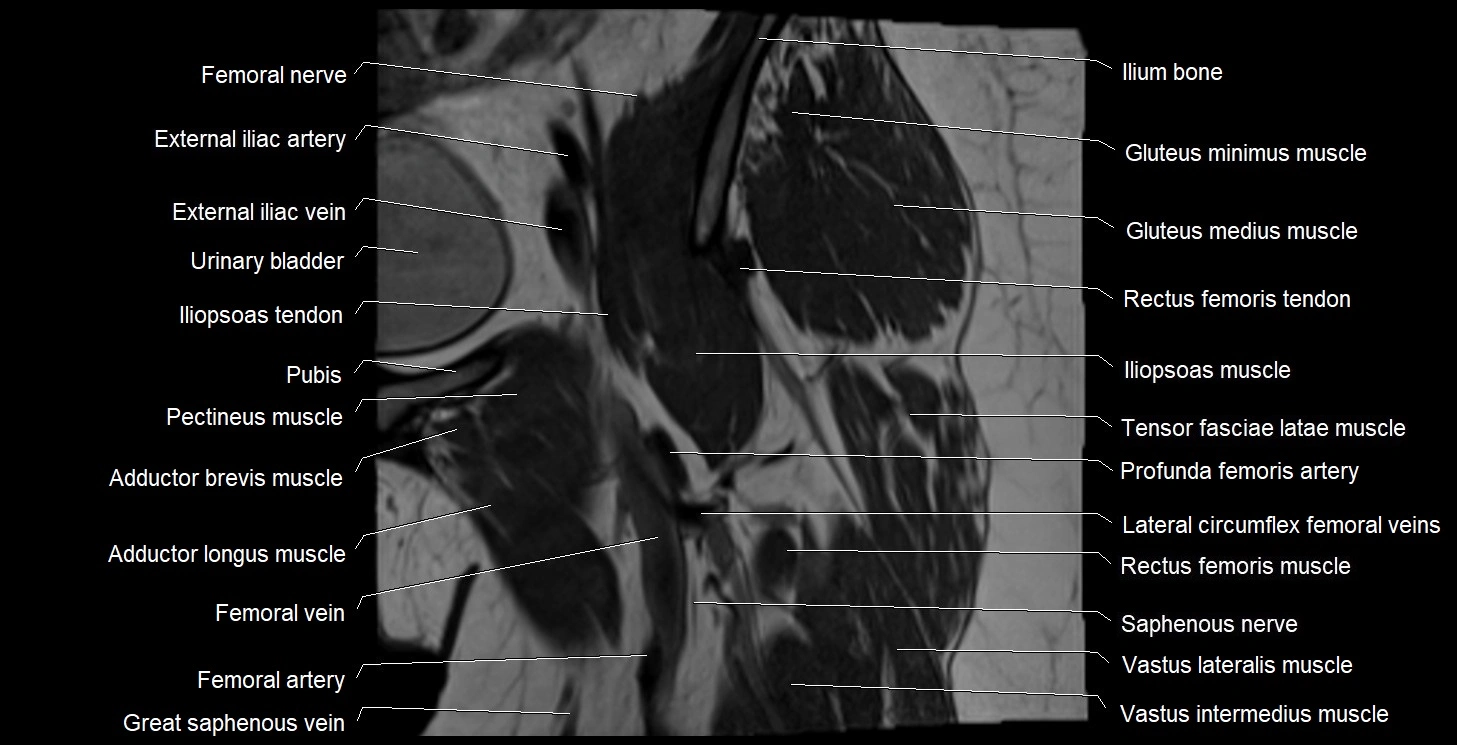

- Femoral nerve

- Femoral vein

- Femur

- Gluteus medius muscle

- Gluteus minimus muscle

- Iliopsoas tendon

- Iliotibial tract

- Ilium bone

- Lateral circumflex femoral veins

- Lateral femoral cutaneous nerve

- Rectus femoris muscle

- Rectus femoris tendon (Proximal tendon of rectus femoris)

- Saphenous nerve

- Tensor fasciae latae muscle

- Urinary bladder

- Vastus intermedius muscle

- Vastus lateralis muscle

- great saphenous vein